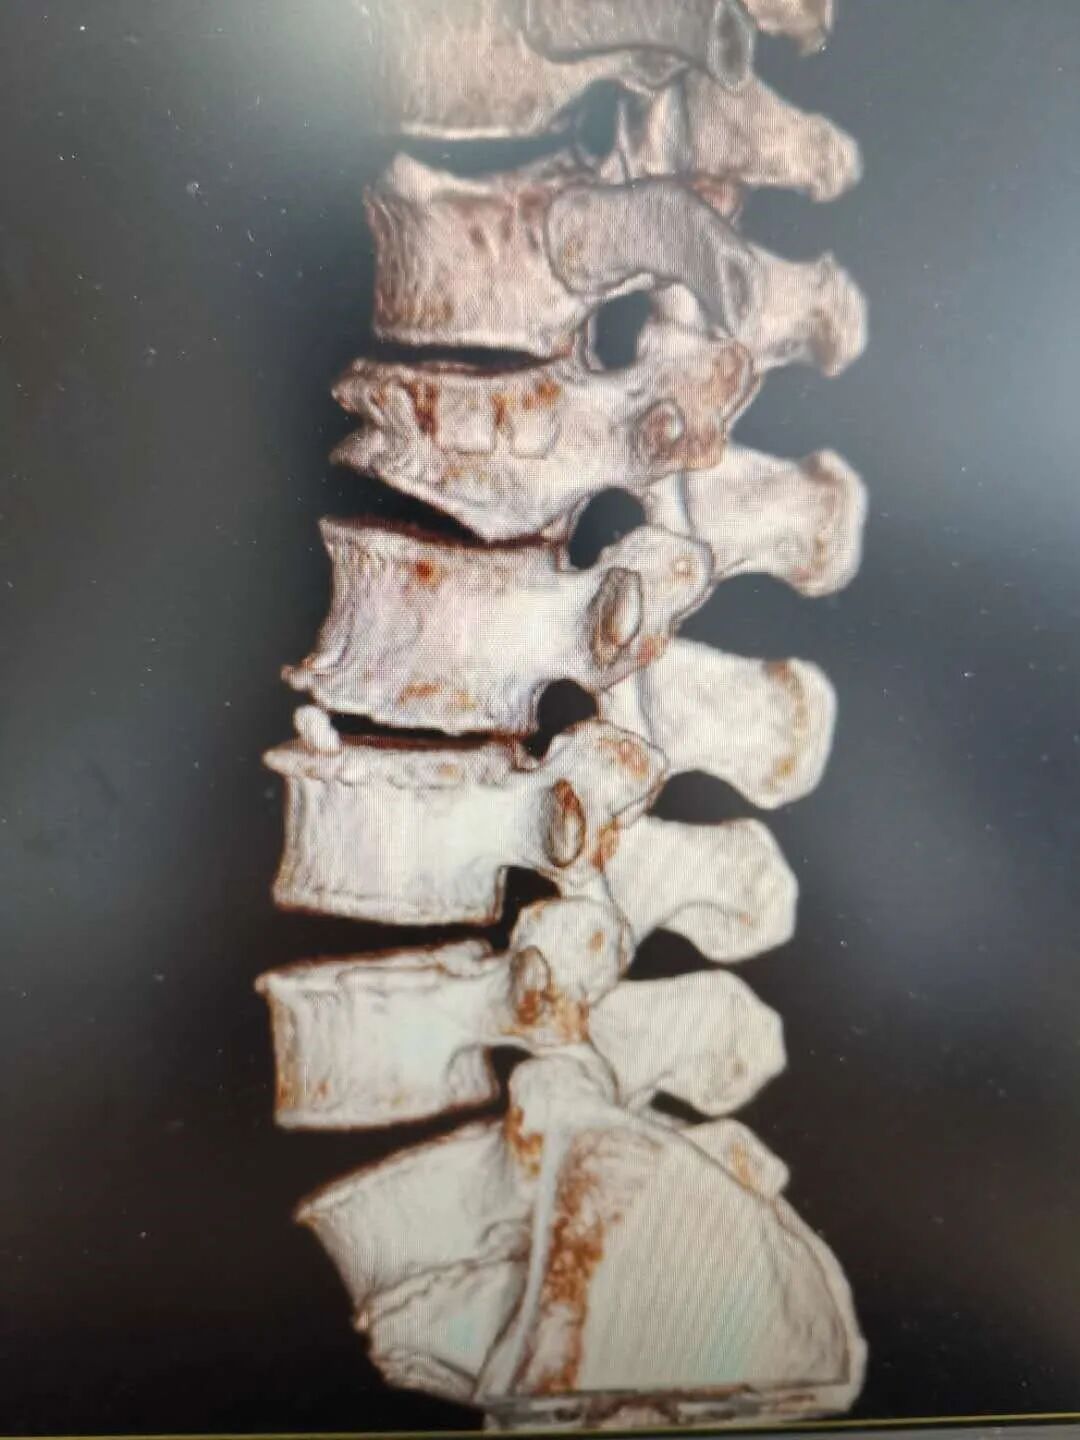

54岁的丁先生,在工地干活时不慎从2米高的高处坠落,臀部着地,当时丁先生只觉得腰部剧痛,不能自如活动,随即由工友送到了海宁康华医院骨2科就诊。 经过CT检查,发现丁先生腰1椎骨折,压缩了约1/2,需要立即采取手术。 丁先生考虑到自己是家中重要的劳动力,强烈要求采取创伤小、恢复快的方案进行治疗,以便自己尽快恢复工作。骨2科团队经过认真研究,决定采用微创小切口的方式在脊柱后路用钉棒固定丁先生因骨折压缩的腰1椎体。最终手术顺利完成。 术后经过复查,CT图像提示腰椎高度回复,内固定位置良好,一周后即可下床。 康华医院骨2科主任、副主任医师陈杰介绍,传统处理腰椎骨折手术需要切开皮肤,剥离肌肉,显露椎体结构后,植入椎弓根螺钉固定,存在切口长、椎旁肌肉剥离广泛、术中出血多、术后切口引流量大、术后切口疼痛、恢复期长等一系列的问题。 而像丁先生这样采取经皮微创植入椎弓根钉棒固定的手术,因其手术创口小(约1cm*6),术中出血少,不剥离椎旁肌肉,术后切口无需引流,无术后切口疼痛,可早期下地进行功能恢复,是近年来发展起来一项技术,也是近年来治疗腰椎滑脱、胸腰椎骨折、椎管狭窄等脊柱疾病采用的一种手术方式。 因为是微创技术,对手术技术要求比传统手术方式更高,术前需要非常周密的计划,根据患者的影像资料做非常精确地测量和定位,更需要手术医生具有非常娴熟技术,因此之前只有一些三甲大医院才有开展。近年来,骨2科在陈杰主任带领下,刻苦钻研,不懈追求,不断精进,希望能以更精湛的技术,温馨的服务,竭力为广大患者解除病痛。